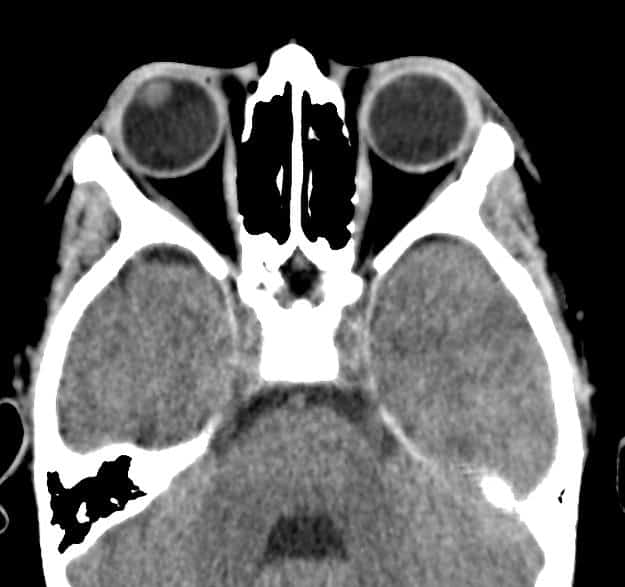

Đục thủy tinh thể trái

Chấn thương nhãn cầu

» Thông tin: Nam giới – 10 tuổi.

» Lâm sàng: Mù mắt phải sau chấn thương.

# Thủy tinh thể phải giảm tỷ trọng do phù nề.